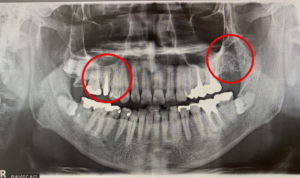

インプラント治療前と後のレントゲン写真です。

こちらが治療前のレントゲン写真です。丸を付けた箇所がインプラント治療を受ける場所です。

左の赤丸は、虫歯の為、歯の根っこが悪くなり抜歯が必要な場所です。(右上4番)

右の赤丸は、歯が抜けたまま放置されていた場所です。(左上7番)